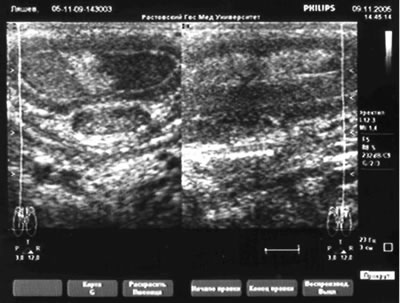

УЗИ

полового члена |

|